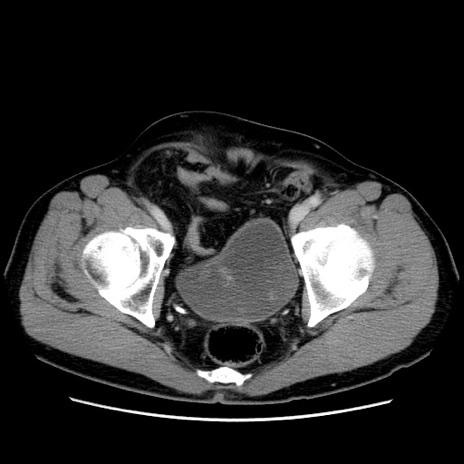

症例34(横断像)

【症例】60歳代 男性

【主訴】右鼠径部膨隆

【現病歴】1年程前より右鼠径部膨隆あり。自己にて還納可能だったため放置していた。3時間前より右鼠径部の脱出を認め、還納困難となり受診。

【既往歴】高血圧

【身体所見】右鼠径部に小児頭大の膨隆あり。弾性硬であり、用手還納は困難。左鼠径部にも膨隆を認める。脱出はなし。

【データ】WBC 15500、CRP 測定なし